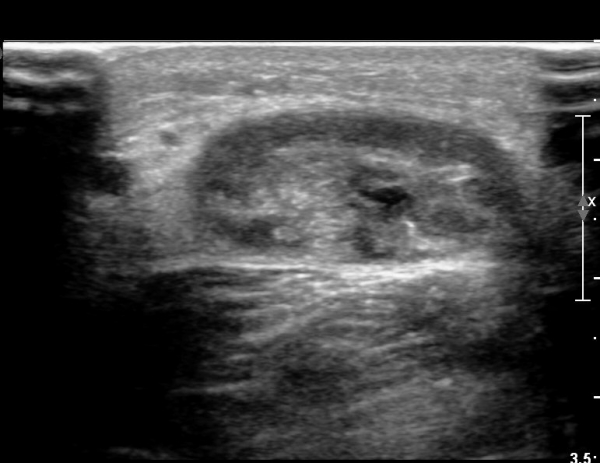

¾ÆÅ³·¹½º°Ç ±ÙÀ§ºÎ Á¾´Ü¸é°Ë»ç¿¡¼­ ¾ÆÅ³·¹½º°ÇÀÇ Àú¿¡ÄÚºÎÁ¾, ±¹¼ÒÀû ¿¬°á¼º ¼Ò½ÇÀÌ °üÂûµÇ¾î

ÆÄ¿­ÀÌ ±¤¹üÀ§ ÇÑ °ÍÀ» º¸¿©ÁÜ(»çÁø 6, 7).

¾ÆÅ³·¹½º°Ç Ⱦ´Ü¸é°Ë»ç¿¡¼­  ¾ÆÅ³·¹½º°ÇÀÇ Àú¿¡ÄÚºÎÁ¾, ±¹¼ÒÀû ¿¬°á¼º ¼Ò½ÇÀÌ °üÂûµÊ(»çÁø 8).